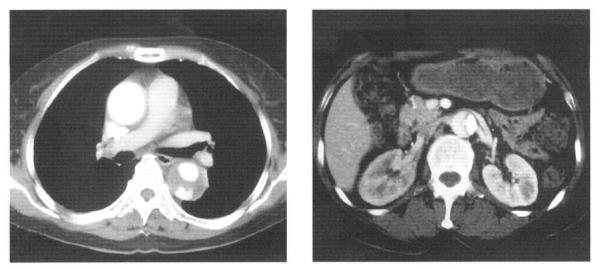

Disseminated intravascular coagulation (DIC) is an acquired coagulation disorder that occurs when the normal hemostatic balance is disturbed, primarily by excessive thrombin formation. Moreover, while DIC is a rare complication of aortic dissecting aneurysm, it is also a well-recognized one. We reported a case of DIC associated with aortic dissecting aneurysm in a 55-year-old woman who was transferred from another hospital because of chest pain radiating to her back and thrombocytopenia. Laboratory findings showed DIC with severe thrombocytopenia, and she was diagnosed as having an acute aortic dissection and DIC. After medical treatment on the aortic dissecting aneurysm, her DIC profile recovered.

弥散性血管内凝血(DIC)是一种获得性凝血障碍,当正常止血平衡受到干扰时发生,主要是由于凝血酶过度生成。此外,虽然DIC是主动脉夹层动脉瘤的一种罕见并发症,但也是一种广为人知的并发症。我们报告了一例55岁女性患者,她因胸痛放射至背部和血小板减少症从另一家医院转诊而来,被诊断为患有与主动脉夹层动脉瘤相关的DIC。实验室检查结果显示为伴有严重血小板减少症的DIC,她被诊断为患有急性主动脉夹层和DIC。在对主动脉夹层动脉瘤进行药物治疗后,她的DIC指标恢复正常。